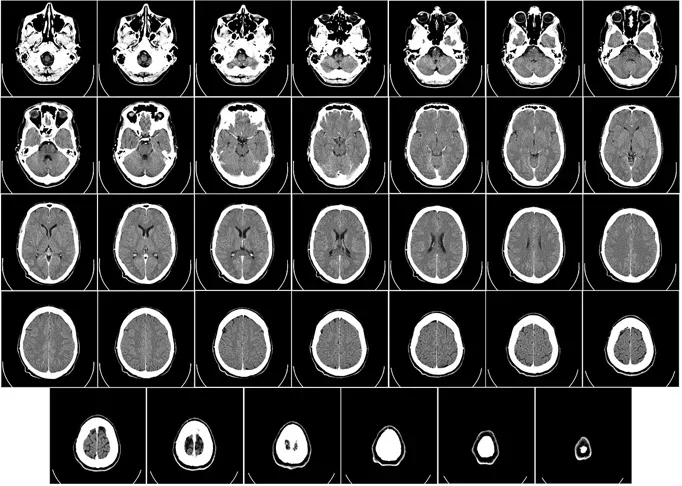

Além da avaliação dos sintomas, o diagnóstico requer exames complementares. Entre eles, tomografia e ressonância magnética. Foto: Imagem de WikiImages por Pixabay -

-